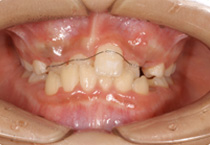

Space Closing

Case 3

Smile Line case 3 2022.06.14

2022.06.14

Smile Line case 3 2022.10.06

2022.10.06

Smile Line case 3 2023.02.07

2023.02.07